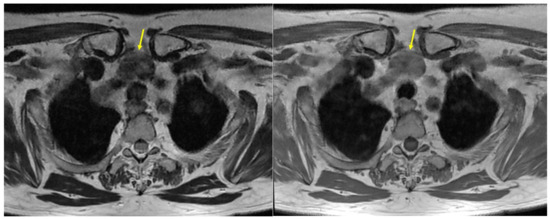

Magnetic resonance imaging (MRI) with intravenous (IV) contrast also confirmed this nodule within the mediastinum, located in the pre-vascular, pre-tracheal compartment of the upper mediastinum on the median line, under the thyroid lobes, but with clear demarcation from them, hence, highly suggesting an ETTM (Figure 2).

Figure 2.

ETTM aspects (yellow arrow): MRI with IV contrast showing a nodule of 2.1 by 2.6 by 3 cm in the pre-vascular compartment of the upper mediastinum on the median line (pre-tracheal): (left) T2 moderate hypo-intensity and (right) T1 iso-intensity.